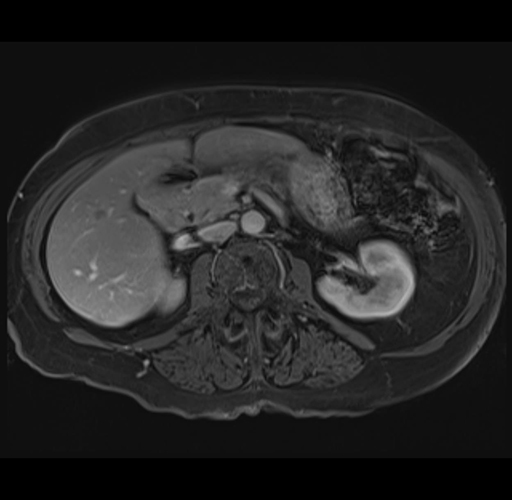

MRI T1